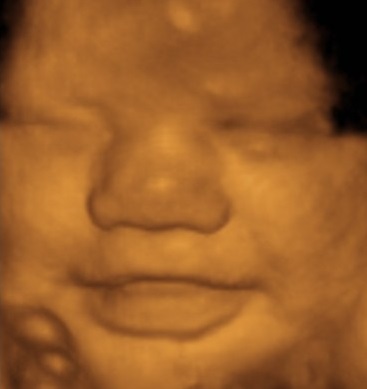

Д Узи Фото